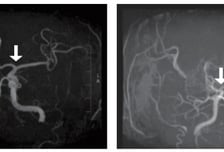

서울대병원 연구팀이 소아 뇌혈관질환인 모야모야병(Moyamoya Disease, MMD)을 혈액 검사만으로 조기에 진단하고 치료 반응을 예측할 수 있는 새로운 바이오마커를 발견했다. 연구팀은 환자의 혈액을 분석해 miR-512-3p라는 특정 마이크로RNA(miRNA)의 수치가 모야모야병 환자에서 대조군에 비해 현저히 높다는 사실을 밝혀냈다. 이 바이오마커는 비정상적인 혈관 생성과 밀접하게 연관돼 있으며, 모야모야병의 조기 진단과 치료 표적으로서 중요한 가능성을 보여준다. 서울대병원 소아신경외과 김승기 교수, ㈜제이엘케이 고은정 박사, 소아암·희귀질환지원사업단 최승아 연구교수 연구팀은 소아 모야모야병 환자의 혈장에서 miR-512-3p라는 새로운 바이오마커를 발굴하고, 그 기능과 작용 기전을 규명한 연구 결과를 31일 발표했다. 모야모야병은 특별한 원인 없이 대뇌에 혈액을 공급하는 내경동맥의 가지치는 부위 혈관이 서서히 좁아지는 만성 진행성 뇌혈관질환이다. 이로 인해 혈류가 부족해지